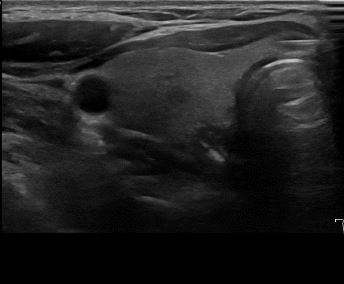

상기환자 목에 불편감 있어 검사위해 내원하신 40대중반 여성분으로

의심스러운 갑상선 협부 결절 세포검사 진행후 갑상선암으로 진단되었습니다